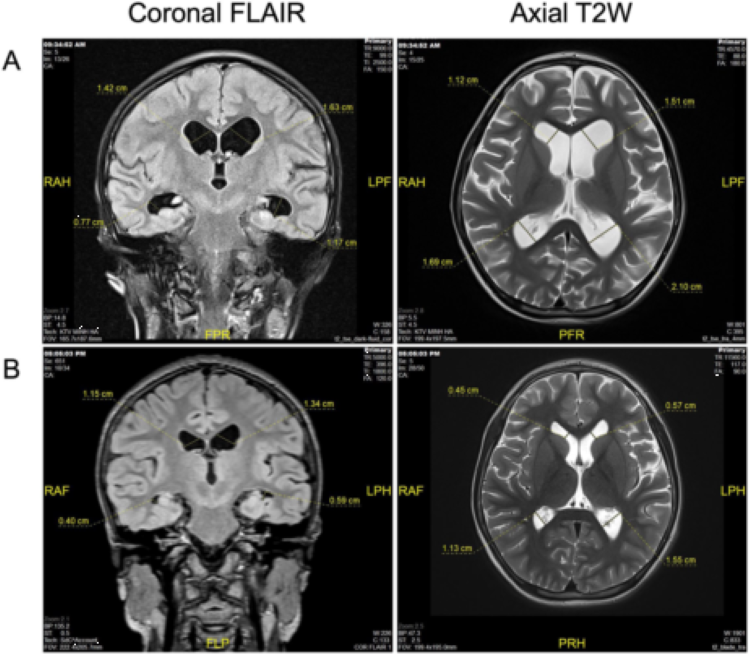

Figure3.患者治療前和三次UC-MSC輸注后的MRI圖像

(A)第一次移植前MRI顯示彌漫性腦萎縮,第三腦室和雙側腦室擴張。(B)在三次UC-MSC注射后,觀察到側腦室、蛛網膜下腔和溝輕度擴張,改善了大腦MRI圖像。MRI:磁共振成像;UC-MSC:臍帶來源間充質干細胞/間質細胞。